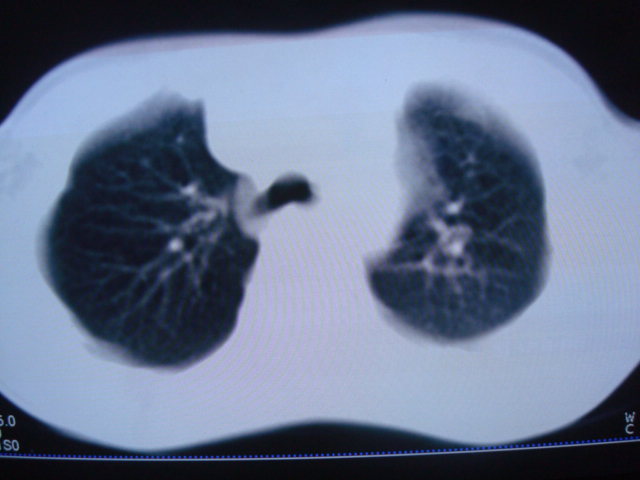

男,10岁,左胸痛,发热轻,血象高。后到省级权威医院治疗,病情明显好转,结果几天后公布。老机器,图像质量差,见谅。

考虑血源性肺脓肿或韦氏肉芽肿

考虑血源性肺脓肿

血源性肺脓肿可能。

考虑化脓性肺炎。